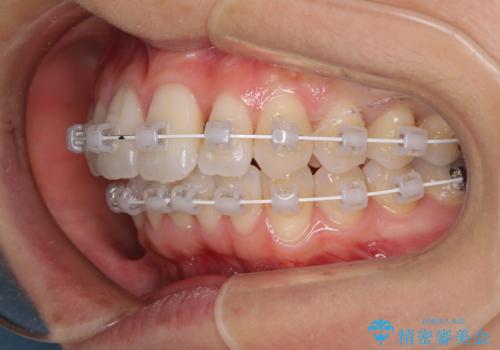

- 矯正装置

- 審美装置

上顎前歯の叢生が解消されると出っ歯になることが分かっていたので、両側奥歯付近にアンカースクリューを入れ、出っ歯を改善するためのゴムかけを行いました。